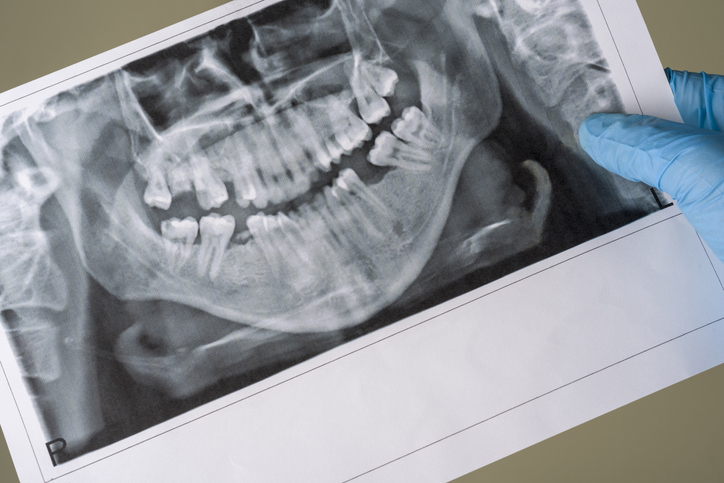

3. X-ray로도 보이지 않는 초기 충치

충치는 어느 날 갑자기 생기지 않습니다. 보통 충치가 X-ray에서 보이려면 치아의 50% 이상이 부식되어야 합니다.

그 전까지는 스스로 관리하면서 예방해야 하며, 6개월 주기의 정기 검진이 권장됩니다.

검진 때 발견되지 않았다고 해서 안심해서는 안 되며, 생활 습관을 바꾸고 치아 관리를 더욱 철저히 해야 합니다.